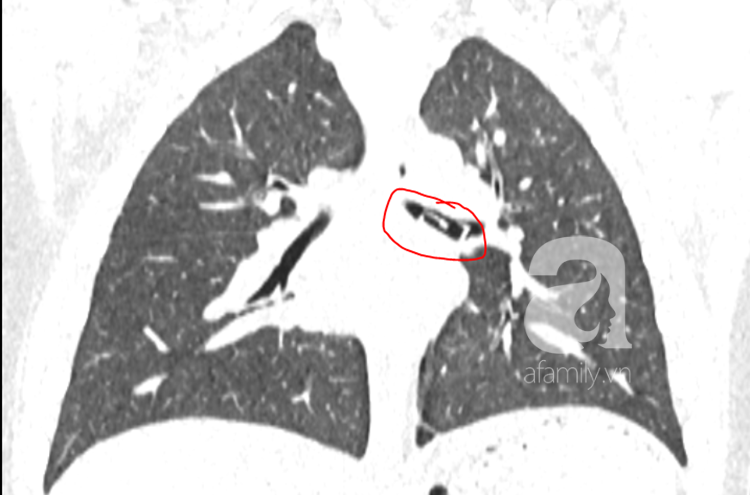

Ảnh chụp phổi cho thấy dị vật bên trong phế quản.

Bệnh nhi được chỉ định chụp CT ngay sau đó. Trên phim CT, ghi nhận ở phế quản trái có một khối dị vật hình chữ nhật, kích thước 1x2cm.